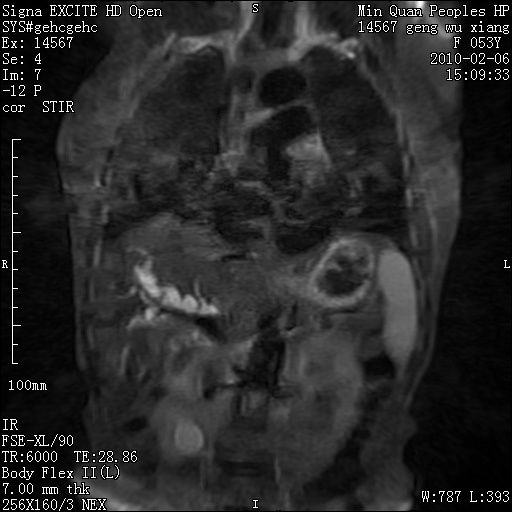

标题: MRI2762:胆道梗阻原因?

f,53y,全身黄染多日。

高位胆道梗阻 胆管癌可能性大

支持 高位胆道梗阻 胆管癌可能性大。